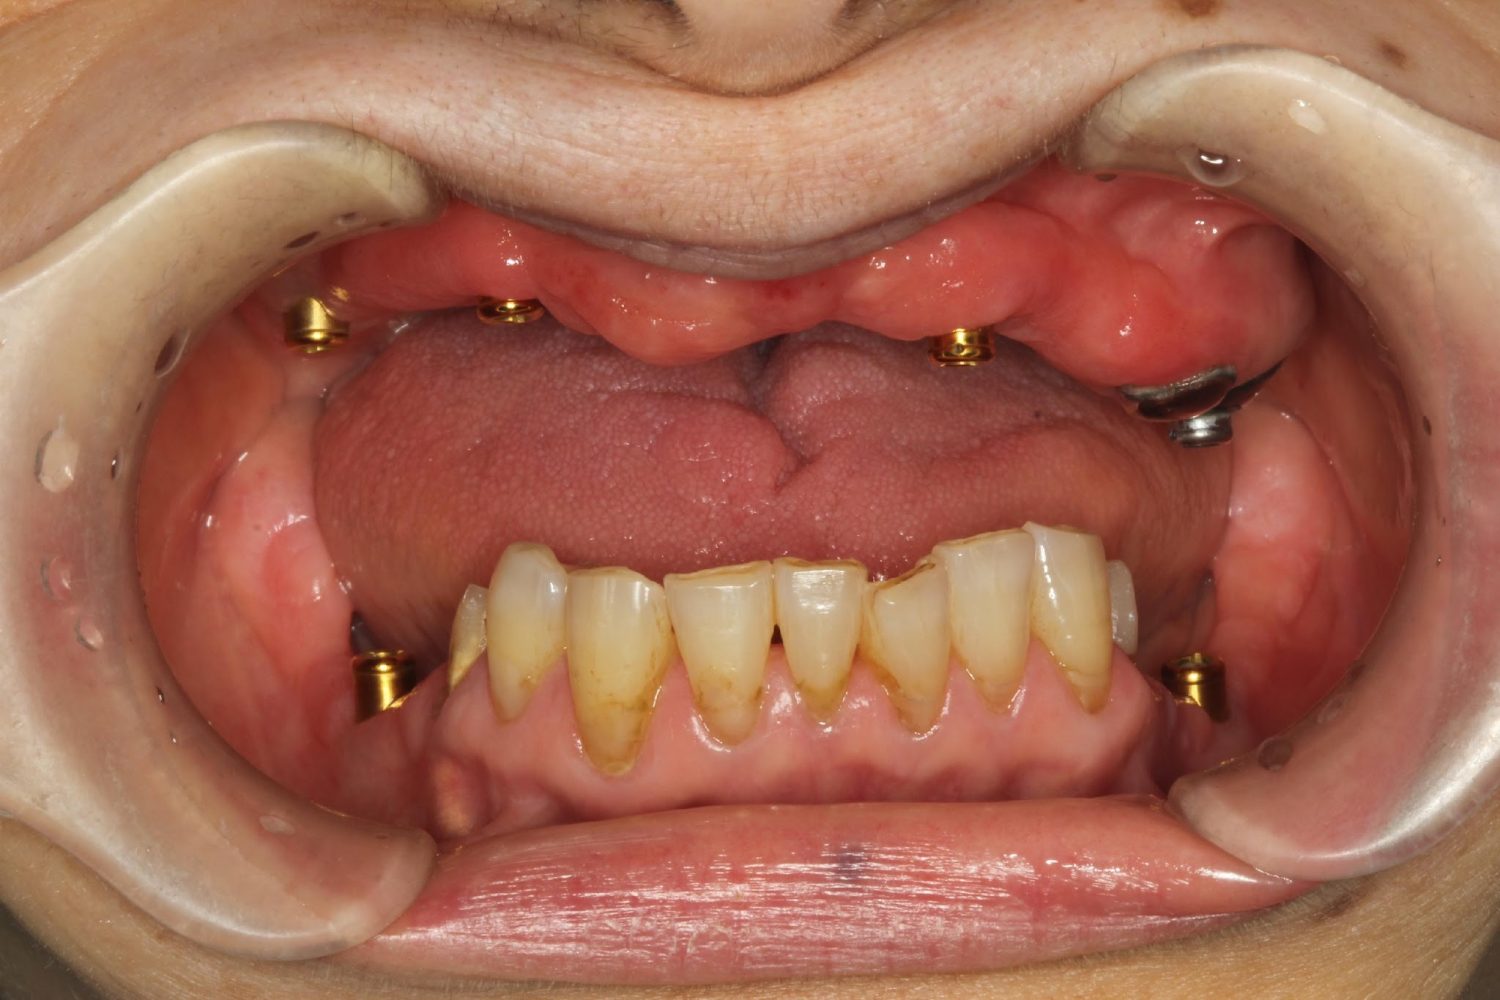

インプラント治療の症例紹介⑤

Before

After

主訴

歯肉腫脹、咬めるようにしたい

治療内容

重度歯周病により全ての残存歯保存不可能な状態。上下顎ボーンアンカードブリッジによる咬合再構成。

治療費

12,621,400円(税込)

治療期間

22ヶ月

通院回数

28回

想定されたリスク

※上部構造の形態が複雑になるため清掃が難しくなる、インプラント周囲炎の恐れがありました。

濱 仁隆先生

浜歯科

上顎8本下顎7本のインプラント体埋入によるボーンアンカードブリッジ。